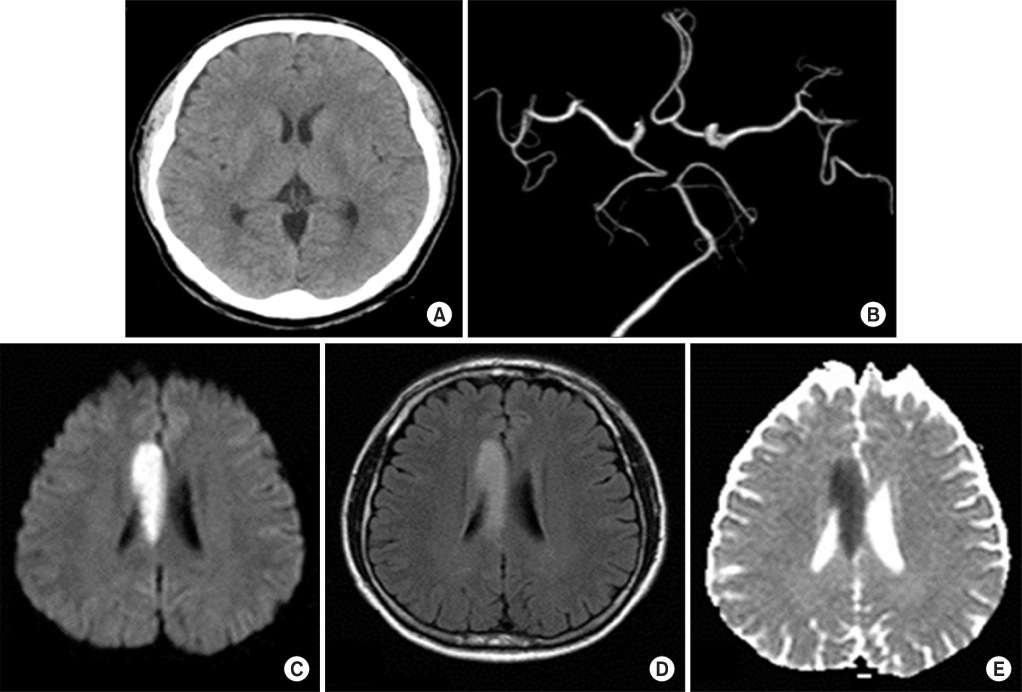

6/L), CK 363 U/L (normal range, 26~140 U/L), CK-MB 26.2 ng/mL (normal, <3.61 ng/mL), and N-terminal prohormone of brain natriuretic peptide (NT pro-BNP) 6,388 pg/mL (normal range, 0~125 pg/mL). Transthoracic echocardiography (TTE) showed mild left ventricular (LV) dysfunction (ejection fraction [EF], 45~50%) (

Fig. 1), regional wall motion abnormality (RWMA) suggestive of multi-vessel coronary artery disease and LV hypertrophy, and left atrial enlargement. Coronary angiography (CAG) showed no significant stenosis at three major coronary vessels.

He was treated conservatively. Two days later, cardiac MRI demonstrated near-normal LV function and no myocardial damage. On the same day, the patient exhibited dysarthria. A brain CT, angiography, and MRI showed no major vessel obstruction but acute infarction on the body of the right corpus callosum (

Fig. 2). By day 11 of hospitalization, dysarthria was fully recovered. The patient was discharged the next day. Eight months later, TTE showed normal LV function and totally recovered RWMA (

Fig. 1). The patient took aspirin, clopidogrel, perindopril, furosemide, aldactone, trimetazidine, and bisoprolol for one year, followed by aspirin, clopidogrel, perindopril through an outpatient clinic.

Fig. 1Electrocardiogram (ECG), chest X-ray and transthoracic echocardiography (TTE) findings at first admission. Initially, (A) ECG shows non-specific ST change, and (B) chest X-ray shows pulmonary edema. (C-1) TTE reveals mild left ventricular (LV) systolic dysfunction, but (C-2) eight month follow-up TTE after first admission demonstrates complete recovery of LV systolic function.

Fig. 2Brain imaging studies at first admission. Brain computer tomography (CT) (A), brain CT angiography (B), brain magnetic resonance imaging (MRI), diffusion weighted image (C), brain MRI, fluid attenuation inversion recovery (FLAIR) image (D), and brain MRI, apparent diffusion coefficient (ADC) map (E) shows acute infarction on right corpus callosum without major vessel obstruction.